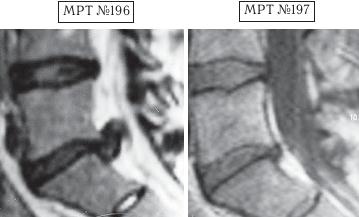

Напомню, что в большом спорте есть большая проблема — это допинги. Допинг в переводе с английского слова «doping» (от dope) означает «давать наркотики». По сути, это в основном химические препараты (фармакологические и другие средства), способствующие стимуляции физической и нервной деятельности на непродолжительное время. Иногда ими пытаются искусственно усилить физическую активность и выносливость спортсмена на время спортивных соревнований. В зависимости от специфики спортивной деятельности в качестве допинга могут использоваться, например, симпатомиметические амины (эфедрин, амфетамин, метиламфетамин и т. д.), стимуляторы центральной нервной системы и восстанавливающие, укрепляющие аналептики (трансамин, стрихнин, лептамин и т. д.), общестимулирующие средства (препараты лимонника китайского, женьшеня, левзеи и т. д.), этиловый алкоголь, наркотики, болеутоляющие средства (морфин, его производные, опиум) и другие препараты. Многие специалисты, не понаслышке знакомые с проблемами большого спорта, отмечают, что современный большой спорт — это уже не старый добрый спорт, где люди показывали свои физические достижения, а это уже во многом соревнование биохимиков по созданию лучшего допинга. Хотя с данной проблемой постоянно борется на международном уровне Всемирное антидопинговое агентство (ВАДА) — независимая организация, созданная при поддержке Международного олимпийского комитета (МОК), каждый год ужесточая антидопинговый контроль, однако всё равно каждый год фарминдустрия выдаёт новые «сюрпризы»-препараты. Печально то, что все эти химические допинги, которые тайно принимает спортсмен для одномоментного улучшения результата, неизменно отражаются на его здоровье, нанося ему ущерб. Ведь весь этот процесс носит экспериментальный характер, а это значит, что последствия для организма вполне могут стать необратимыми, а в некоторых случаях дело может закончиться и летальным исходом, что неоднократно случалось в практике большого спорта. Однако мало кто из спортсменов задумывается в момент приёма допинга о его отдалённых последствиях для своего организма. Многие спортсмены находятся в плену ошибочных стереотипов, которые гласят, что «если не будешь принимать допинг, не сможешь победить». Однако не зря говорится: «Познай себя и ты познаешь весь мир». Возможности человеческого организма многократно превышают возможности искусственной химии. Свидетельством тому является множество известных науке случаев, связанных как со спортом, так и с жизненными обстоятельствами, когда человек в экстремальных, чрезвычайных ситуациях способен проявить такие феноменальные способности и возможности, которые не всякий чемпион сможет повторить. Человеческий мозг — это далеко не изученная, сложная система центрального управления организмом, которая может функционировать в разных режимах, о чём неоднократно упоминается, например, в работах академика Натальи Петровны Бехтеревой. Так что не стоит искать обманчивых путей для достижения высот, ведь ничто не проходит в этой жизни бесследно. Как писал Омар Хайям: «Нищим дервишем ставши — достигнешь высот. Сердце в кровь разорвавши — достигнешь высот. Прочь, пустые мечты о великих свершеньях! Лишь с собой совладавши — достигнешь высот». Так что в любом деле важна внутренняя составляющая человека. Ради справедливости должен заметить, что среди моих пациентов, помимо спортсменов, немало просто самодисциплинированных людей, которые в полной мере ответственно, целеустремлённо подходят к вопросам своего здоровья. Это радует, поскольку понимаешь, что твой труд не пропадёт даром. Ведь если пациент столь тщательно будет следить и беречь своё здоровье и дальше, то организм ещё долго послужит ему верной службой. А это в свою очередь означает, что в жизни данного человека станет намного меньше проблем и он получит полноценную возможность для самореализации. Как говорится в пословице: «Жизнь дана на добрые дела». А тем читателям, кто на сегодняшний день обременён проблемой заболевания позвоночника, хочу сказать, что не стоит отчаиваться. Люди справлялись ещё и с худшими ситуациями. Доказательством тому служат как вышеизложенные, так и нижеприведённые случаи, которые даже высокопрофессиональным специалистам когда-то казались безнадёжными. Думаю, комментарии здесь излишни. Пример № 1. ![]() На МРТ № 192 наблюдается состояние поясничного отдела позвоночника: рецидив после операции — секвестрированная грыжа межпозвонкового диска в сегменте LIV-LV, абсолютный стеноз спинномозгового канала. На МРТ № 193 — состояние поясничного отдела позвоночника после лечения методом вертеброревитологии. Пример № 2. ![]() На МРТ № 194 наблюдается состояние поясничного отдела позвоночника после трёх операций: рецидив — грыжа межпозвонкового диска в сегменте LV-SI стеноз спинномозгового канала. На МРТ № 195 — состояние поясничного отдела позвоночника после лечения методом вертеброревитологии. Пример № 3. ![]() На МРТ № 196 наблюдается состояние поясничного отдела позвоночника после операций: рецидив грыжи межпозвонкового диска в сегменте LV—SI с формированием секвестра с миграцией в краниальном направлении, абсолютный стеноз спинномозгового канала. На МРТ №s197 — состояние поясничного отдела позвоночника после лечения методом вертеброревитологии. Пример № 4.